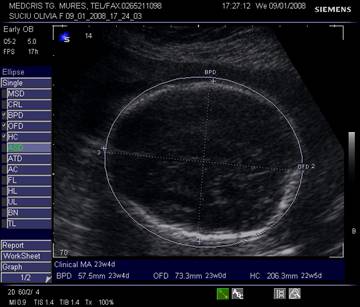

Capul - planul corect de referinta permite masurarea in aceeasi sectiune a celor trei parametri BPD, OFD, HC

Planul

cuprinde o sectiune occipitofrontala transversala simetrica, ovoidala, cu

prezenta distincta a ecoului de mijloc, cavum septum pellucidi in 1/3

anterioara si nucleii talamici .

Fig. nr.198. Masurarea diametrului biparietal ( BPD )

Fig. nr.199. Masurarea diametrului occipitofrontal (OFD ) si a circumferintei craniene ( HC)